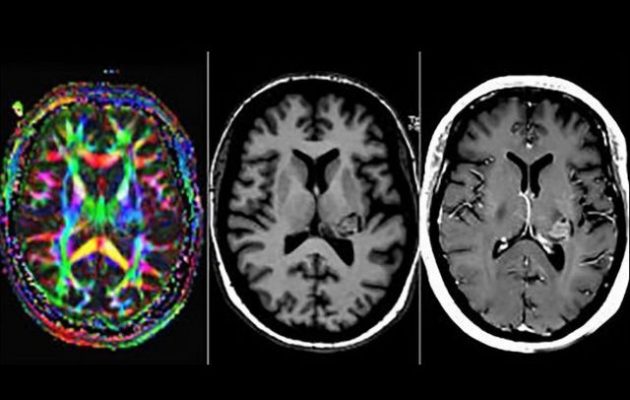

Αρχικά νόμιζαν ότι ήταν ψυχικά ασθενής, αλλά αυτή η «εύκολη» διάγνωση δεν ήταν αρκετή για τους επιστήμονες. Όταν της έκαναν μαγνητική τομογραφία ανακάλυψαν ότι είχε έναν όγκο που μεγάλωνε μέσα στον εγκέφαλό της.

«Ο όγκος εντοπίστηκε σε ένα δίκτυο που είναι ζωτικής σημασίας για την αντίληψη της ομιλίας, για αυτό άκουγε φωνές».